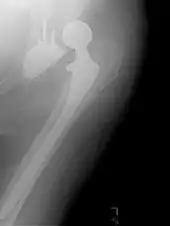

Intraoperative acetabular fracture

Intraoperative fractures may occur. After surgery, bones with internal fixation devices in situ are at risk of periprosthetic fractures at the end of the implant, an area of relative mechanical stress. Post-operative femoral fractures are graded by the Vancouver classification.